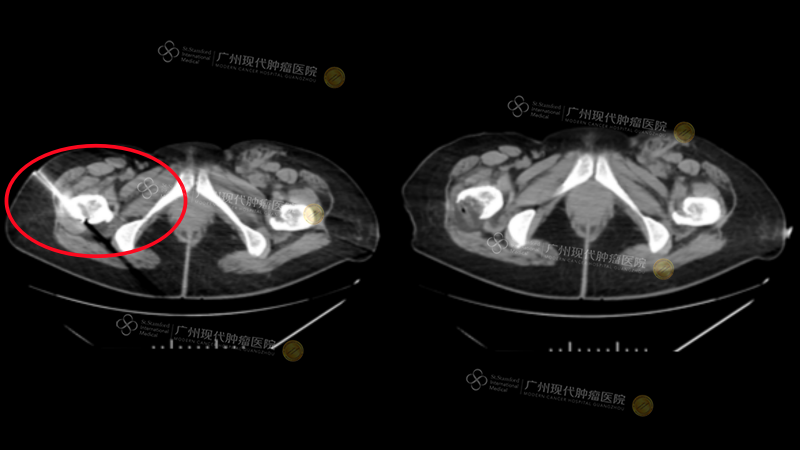

王教授通过一系列典型病例,生动诠释了微创技术的临床应用价值。其中,一例乳腺癌并骨转移患者,治疗前疼痛评分(NRS)高达10分,使用大剂量常规止痛药物仍效果不佳;经MDT讨论后为其施行了CT引导下的冷冻消融术,术后患者疼痛得到显著缓解,生活质量获得明显改善。

●●

(施行冷冻消融术)

(治疗后NRS评分)

另一例乳腺癌术后复发伴胸壁、骨转移的患者,同样面临常规药物镇痛不满意的困境(NRS 8分);在采用放射性粒子植入术后,患者疼痛得到有效控制,生活质量和活动能力(Karnofsky评分)均较前提升。

(施行粒子植入术)